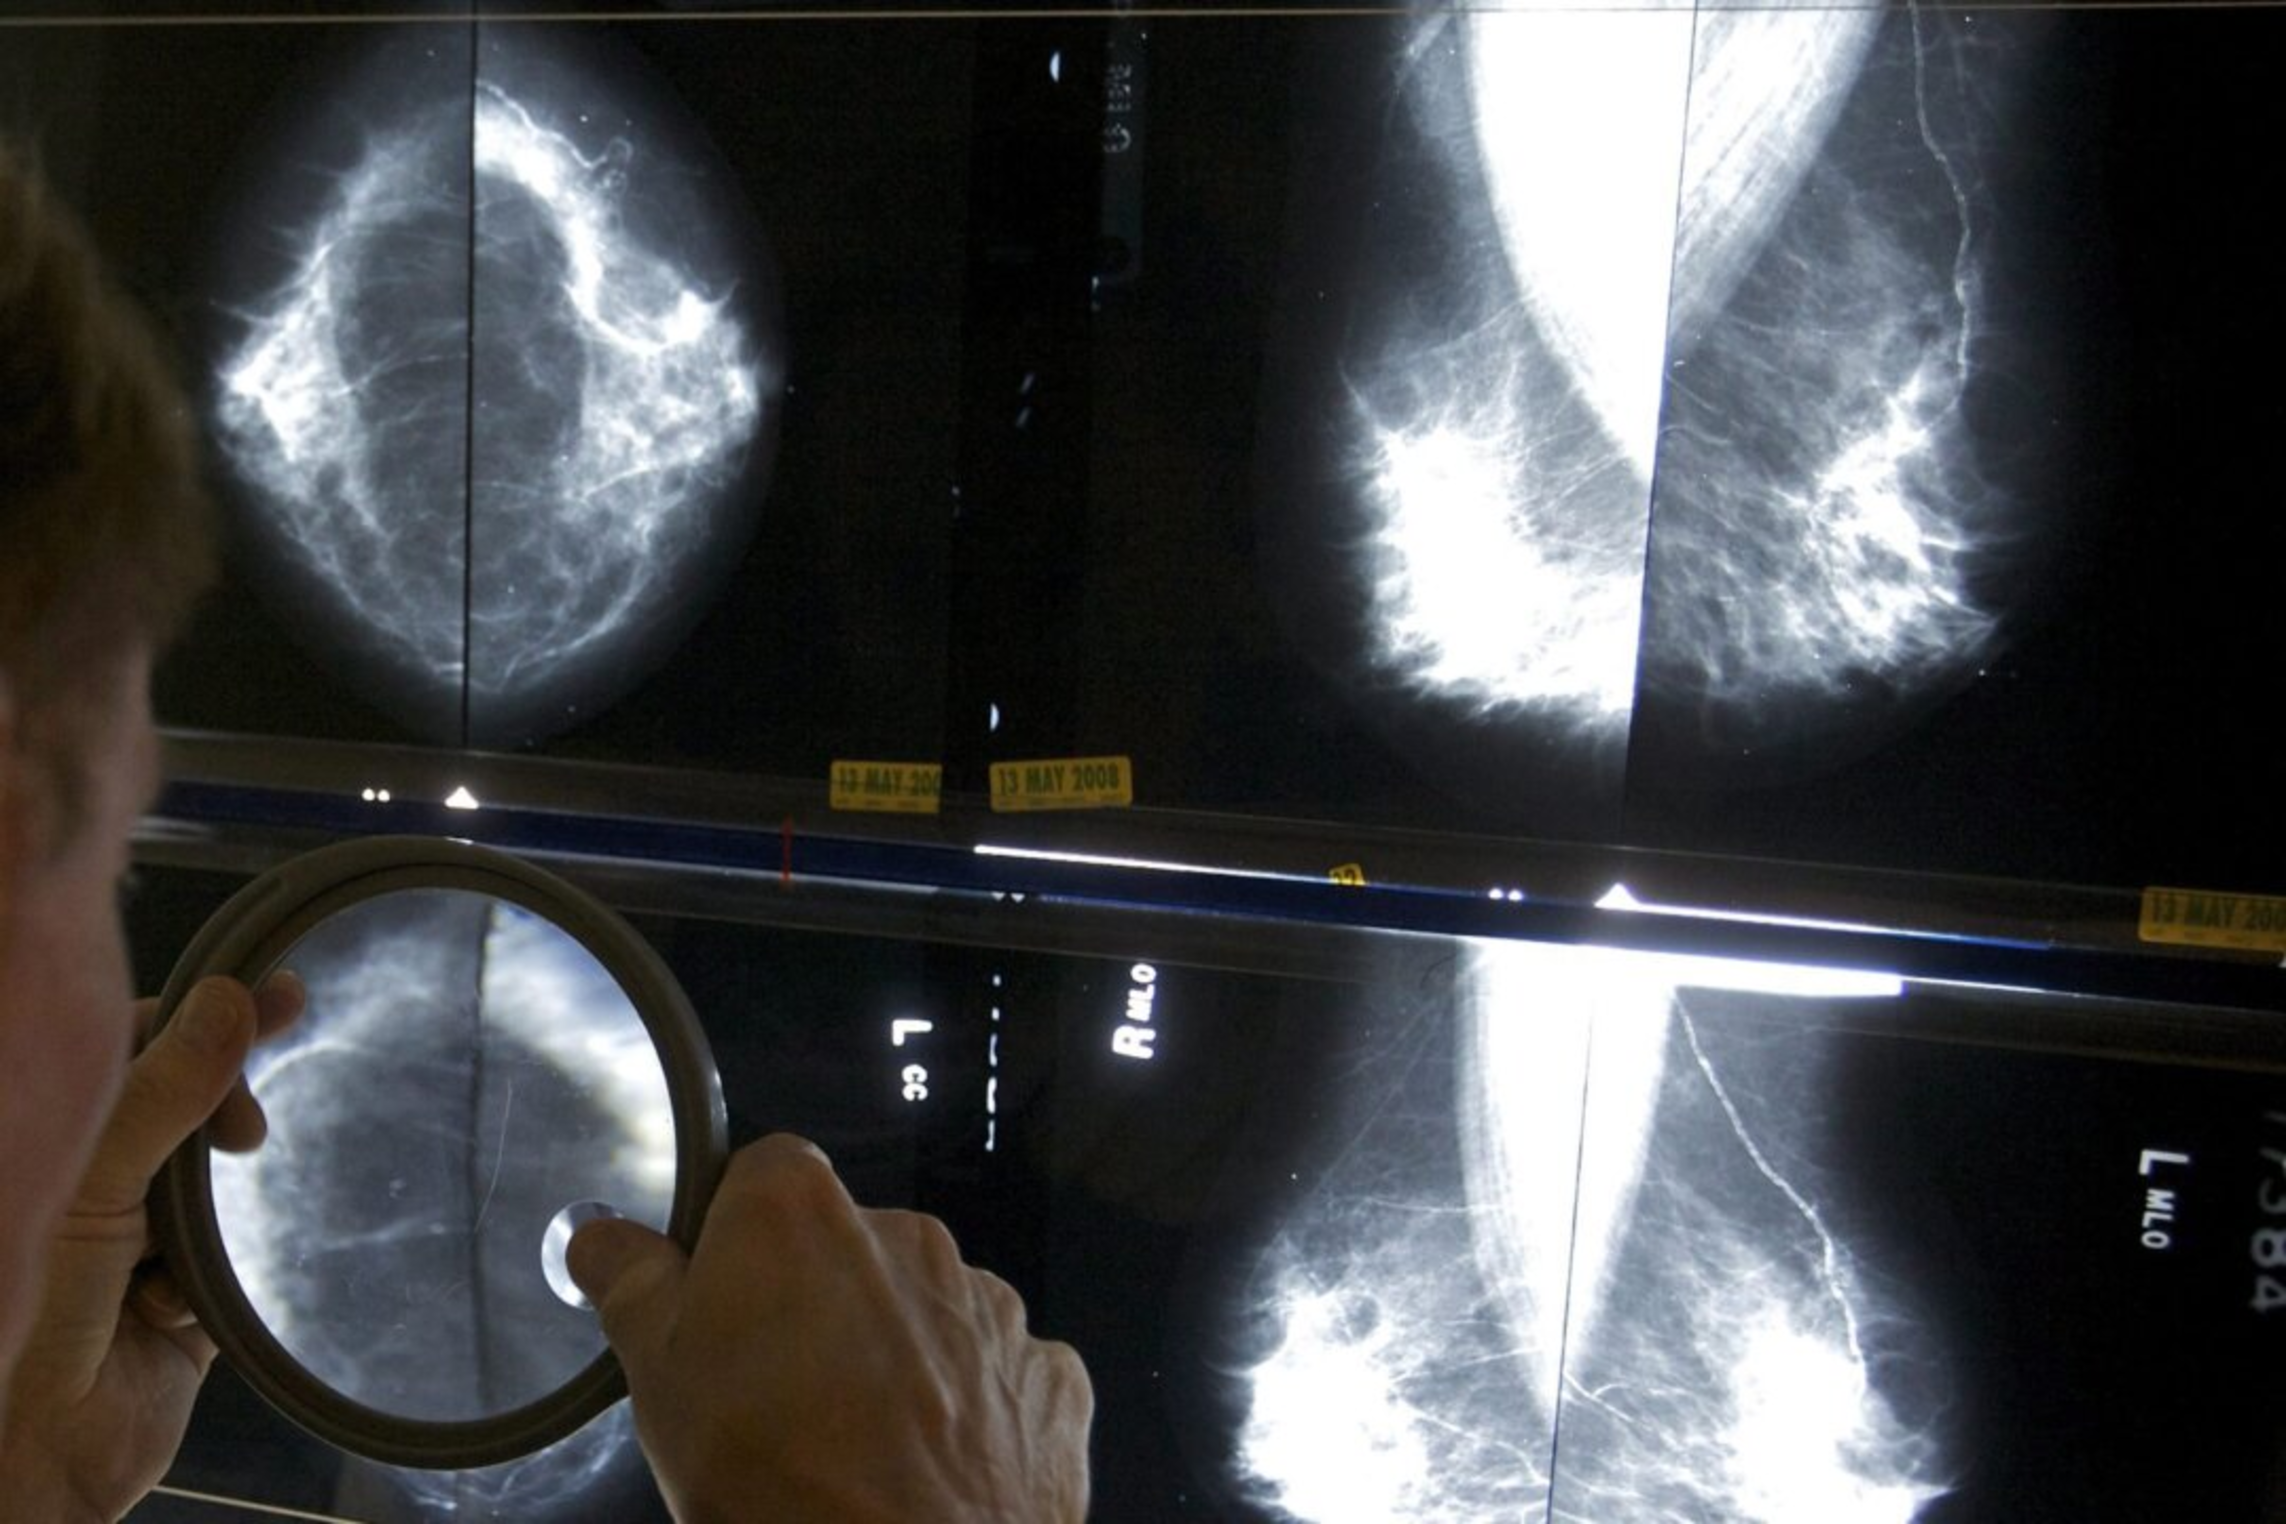

Cancer cases and deaths are expected to increase in 2024, according to a recent study from the Canadian Medical Association Journal. “Although the overall incidence of cancer and associated mortality are declining, new cases and deaths in Canada are expected to increase in 2024, largely because of the growing and aging population,” said the May 13 study “Projected Estimates of Cancer in Canada in 2024.” The study said in 2024 there will be an estimated 247,100 new cancer diagnoses and 88,100 cancer deaths, which is up from 239,100 cases and 86,700 deaths in 2023. Lung cancer is expected to be the most common cause with 20,700 deaths, compared to colorectal cancer (9,400 deaths), pancreatic cancer (6,100), breast cancer (5,500), and prostate cancer (5,000)....